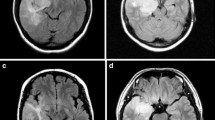

Pilocytic astrocytomas usually appear on CT scans as round/oval lesions that are well-defined iso- or slightly hypo-dense and markedly enhance with contrast media. On MRI, PAs are typically hypo- or iso-intense on T1 sequences and hyperintense on T2-weighted or FLAIR images. They are typically strongly and diffusely enhancing (Fig. 1a–f). They may contain cysts or consist of a tumor nodule in a cyst (the latter being particularly common for cerebellar and hemispheric tumors) (Fig. 1b, d, e). Pilocytic astrocytoma, involving the optic pathways, optic nerve, and chiasm, typically form fusiform masses. It is the most common site in NF1 patients in whom bilateral tumors may arise (Fig. 2a). In the posterior fossa, PA may involve primarily the brainstem rather than the cerebellum. At this site, in contrast to diffuse intrinsic pontine gliomas, which infiltrate and expand primarily within the pons, PAs are generally located dorsally and have an exophytic pattern of growth (Fig. 1c) [20]. The spinal cord can also be affected (Fig. 1f) [44, 45].

Pilocytic astrocytoma, with its characteristic imaging features, may occur virtually at any site in the CNS. Six different examples (all histologically confirmed) with strong contrast enhancement are illustrated: two cerebellar examples, one of a small left para-vermian well-circumscribed and solid tumor (a) and one of a cystic tumor with a mural nodule (b); a “dorsally exophytic” midbrain PA (c); a cyst with a mural nodule occupying the right thalamus (d); a peripheral solid and cystic tumor in the right parietal lobe (e); and a large, circumscribed, intramedullary, tumor with a cystic component (f)